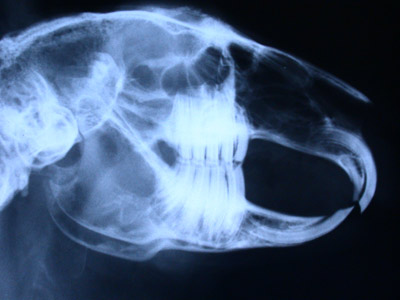

Schädel Kaninchen Überprüfung der Zahnwurzeln